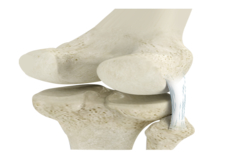

Articular Cartilage and Menisci of the Knee

Movement of the bones causes friction between the articulating surfaces. To reduce this friction, all articulating surfaces involved in the movement are covered with a white, shiny, slippery layer called articular cartilage. The articulating surface of the femoral condyles, tibial plateaus and the back of the patella are covered with this cartilage. The cartilage provides a smooth surface that facilitates easy movement.

Within the knee joint, between the femur and tibia, are two C-shaped cartilaginous structures called menisci. Menisci function to provide stability to the knee by spreading the weight of the upper body across the whole surface of the tibial plateau. The menisci help in load-bearing i.e. it prevents the weight from concentrating onto a small area, which could damage the articular cartilage. The menisci also act as a cushion between the femur and tibia by absorbing the shock produced by activities such as walking, running and jumping.